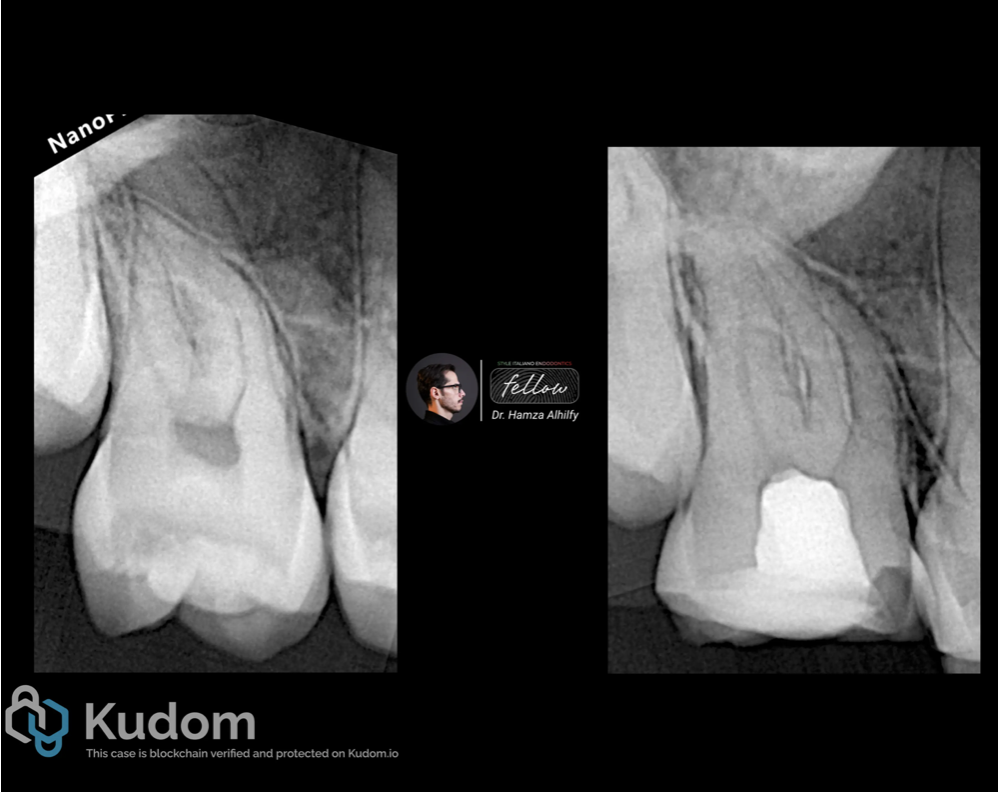

Fig. 1

Patient came to my clinic complaining from slight sensitivity from sweets and cold drinks in the lower right second molar. After performing cold test the tooth responded for 15 second to cold then the sense disappeared.

Radiographic x-ray shows normal periapical area with no sign of pathology.

Fig. 2

Pre and post operative x-ray images .